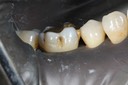

Mark Chun #18 pre-op

Mark Chun #19 caries removal